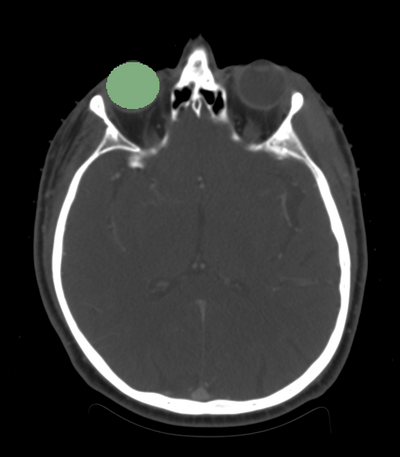

segmentation of eye ball axial view

• We are interested in segmenting the eye ball, lens, optic nerve, and the optic chiasm.

• We have the eye ball segmentation.